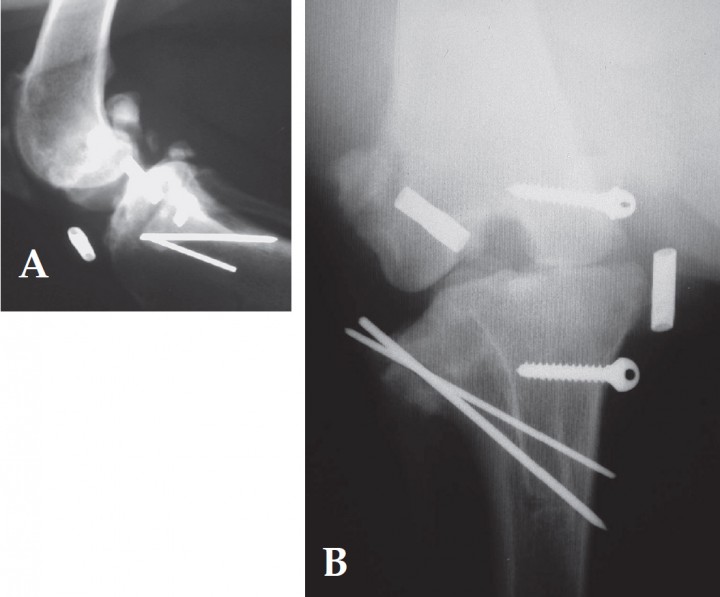

Se posicionó el paciente en decúbito dorsal y se realizó la preparación aséptica del campo operatorio. La articulación fémoro-tibio-rotuliana fue abordada lateralmente, realizando la recolocación del fragmento fracturado mediante su deslizamiento de lateral a su posición original, por debajo del tendón del músculo extensor digital largo, respetando la integridad de la vaina y del tendón con la finalidad de mantener su correcta función motora. El fragmento óseo se recolocó, y se mantuvo en el lugar que le corresponde con una pinza sujeta-huesos; a continuación se fijó, en un primer y único intento, con dos agujas de kirschner de 1.5 y 1.2 mm de diámetro respectivamente (introducidas con un taladro a bajas revoluciones e irrigando con suero fisiológico en todo momento para evitar la necrosis térmica) en sentido latero-medial en modo cruzado (Figs. 3 A y B). Deliberadamente, las agujas se dejan largas para facilitar su retirada cuando la fractura esté resuelta. La aguja de menor calibre se recorta desde el subsiguiente acceso medial, desde el cual se resuelve la rotura del ligamento colateral medial. Las agujas no se doblan en su extremo proximal para evitar el colapso y desgajamiento del fragmento.

<p>Radiografías postoperatorias. A. Proyección lateral B. Proyección postero-anterior.</p>

Figura 4

Radiografías postoperatorias. A. Proyección lateral B. Proyección postero-anterior.